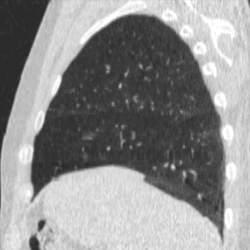

Four-dimensional computed tomography (4DCT) is a type of CT scanning which records multiple images over time. It allows playback of the scan as a video, so that physiological processes can be observed and internal movement can be tracked. The name is derived from the addition of time (as the fourth dimension) to traditional 3D computed tomography. Alternatively, the phase of a particular process, such as respiration, may be considered the fourth dimension.[1]

4DCT is used in radiation therapy planning to reduce doses to healthy organs such as the heart or lungs. Most radiation therapy is planned using the results of a 3D CT scan. A 3D scan largely presents a snapshot of the body at a particular point in time, however due to the time of the acquisition, in which the patient is likely to have moved in some way (even if only breathing), there will be an element of blurring or averaging in the 3D scan.[6] When it comes to treatment planning, this motion can mean there is less accuracy in the positioning of treatment beams, and reduce the likelihood of a repeatable set-up on the linear accelerator when it comes to treatment.[7]

To minimise physical movements of the patient, some sort of immobilisation is typically used. To overcome physiological motion, such as breathing, 4DCT acquires images at a range of times and positions, allowing the extent of motion to be visualised (e.g. from maximum inspiration to maximum exhalation). The treatment plan can then be designed with a knowledge of the full range of possible positions of important organs, and the tumour (target) itself.[8]